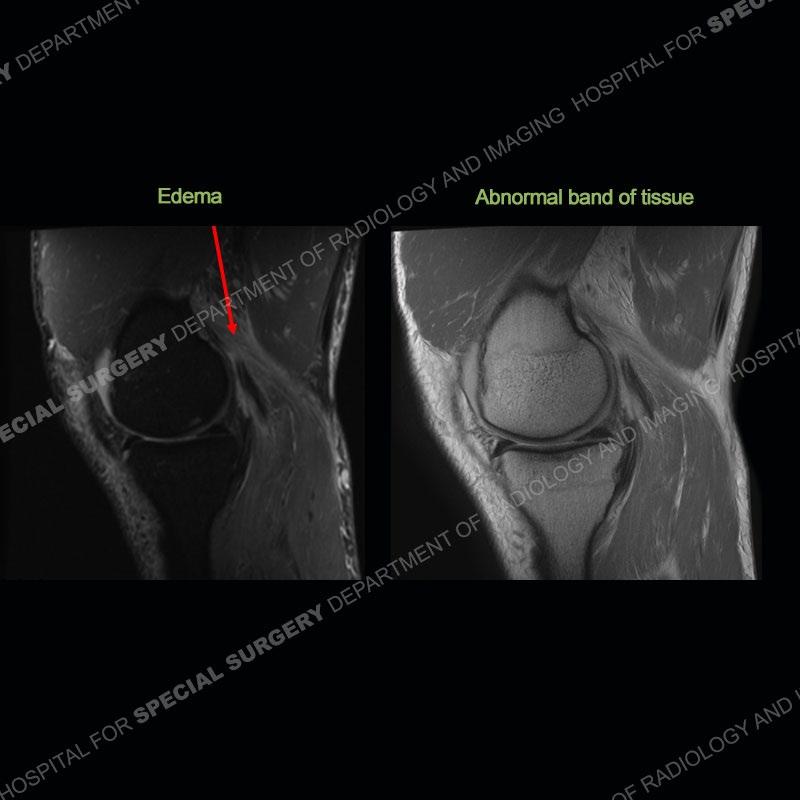

The radiographs show degenerative change of the medial compartment and a varus knee, but they are not germane to this case. No acute bony injury is present. The MRI shows edema of the posterior medial knee/soft tissue and a focal area of a partially disrupted low signal structure. The details are kept at a minimum in the findings of this case on purpose.

Fourth, use all imaging planes and different pulse sequences to make your diagnosis. The edema highlighted in this case can be seen as the obscuration of fat on the PD images but is much easier to perceive as the high signal on the IR pulse sequences. The actual disruption of the MHG myotendinous junction is only able to be seen on the axial images. On the sagittal and coronal images, we get a sense something is wrong but hard to be exact. Lastly, when you look at a study and something just seems off (as I would say the sagittal and coronal images do with that dark band of tissue posteriorly), listen to yourself and go through the study slowly and meticulously. Most of the time you will find you were right, and something indeed is present.